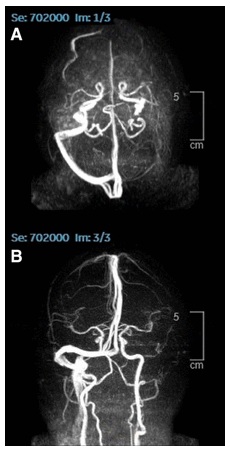

Eine 25jährige, die bereits in der Vergangenheit an Multipler Sklerose erkrankt war, wird in einem Krankenhaus vorstellig, weil es ihr seit fünf Tagen nicht mehr möglich ist, den linken Fuß zu benutzen, sie ihn nur hinterherziehen kann. Sie berichtet, dass sich ihre linken Extremitäten seit Tagen steif anfühlen und nicht belastbar sind. Die Symptome bleiben auch in den nächsten Tagen konsistent. Fünf Jahre zuvor war bei der 25jährigen Multiple Sklerose diagnostiziert, mit Hilfe von Steroiden aber vollständig zum Verschwinden gebracht worden. Dem Wiederaufflammen von Multipler Sklerose war unter anderem die Impfung mit Johnson&Johnsons Adenovirus basiertem Impfstoff vorausgegangen. Eine Kernspintomographie zeigt eine Reihe von Flüssigkeitsansammlungen im Gehirn der Patientin:

MS kommt wieder nach der

SCHLANGENGIFTimpfung, Flüssigkeitsblasen im Hirn

MS kommt wieder nach der SCHLANGENGIFTimpfung, Flüssigkeitsblasen im Hirn [2]

T2-weighted MRI images of the brain. A & B: Axial images of brain MRI demonstrating several foci of FLAIR hyperintensities (red arrows); C: Sagittal image of brain MRI showing large FLAIR in right posterior frontal lobe measuring 1.4 cm (red arrow). Quelle. Al-Midfai et al. (2022).

Multiple Sklerose ist eine Autoimmunerkrankung, die das zentrale Nervensystem schädigt. Das Wiederaufflammen von Multipler Sklerose bei der 25jährigen wurde von einer akuten, entzündlichen demyelisierenden Reaktion im zentralen Nervensystem begleitet, also einer Zerstörung der Myelinscheide von Nervenzellen. Im vorliegenden Fall ist das Wiederaufflammen von Multipler Sklerose nach Ansicht der Autoren auf die vorausgehende Impfung mit dem Adenovirus-basierten Impfstoff von Johnson&Johnson zurückzuführen.